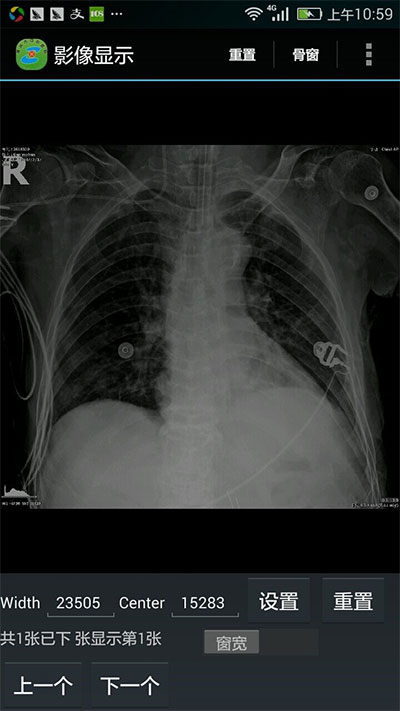

通过技术人员近一年的开发实践,中心医院掌上医疗项目开发完成,实现了病人全信息的查询功能:能展示病人的体温单、医嘱单、入院记录、病程记录、手术记录、出院记录、检验检查报告单、医学影像、窗位变换等。

湖州中心医院一直致力于医疗信息化建设,加快医生诊断、检查流程,提高病人就医体验,为了使医生能够随时了解并掌握病人的实时信息,医院决定引入掌上医疗,并为医生配备了业务手机,方便医生及时获取病人的诊疗数据。但dicom数据的读取一直以来难以移植到移动端,尤其图像处理这一部分的开发是比较有难度的,目前业界在移动端上连接pacs和展示医学影像的控件就数leadtools比较成熟,能够在手机上显示医学影像文件、更改窗位、连接pacs系统、显示病人信息。大大减少开发难度,节省开发成本。

窗位变换:

窗位变换前 窗位变换后

leadtools medical系列产品支持全平台开发,而且支持通用的dicom、pacs接口,可以跟我们现有的医疗系统实现无缝对接,尤其是android平台下有现成的示例,大大减少了我们研究的时间。而且leadtools产品功能丰富,对我们后续的开发扩展功能提供了灵活的定制能力。